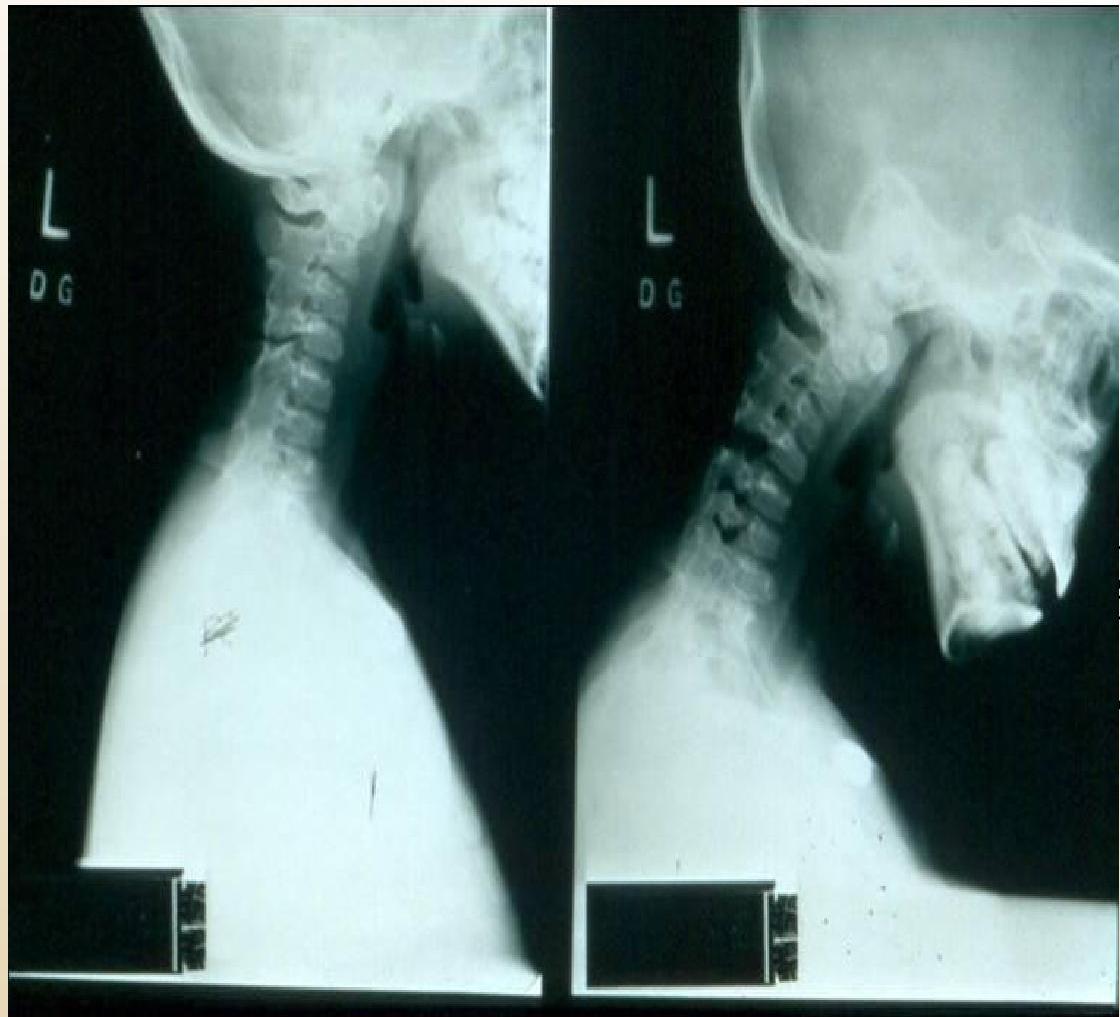

- Cervical Spine:

- Decreased extension is asymptomatic.

- Can lead to subluxation (typically C2 on C3).

- Radiographic: Fusion of neural arch (C2-C3), narrowing/erosion of remaining joints, obliteration of apophyseal space, loss of normal lordosis.

Cervical Spine:

(Left: Fusion of neural arch C2-C3. Right: Flexion/extension views)